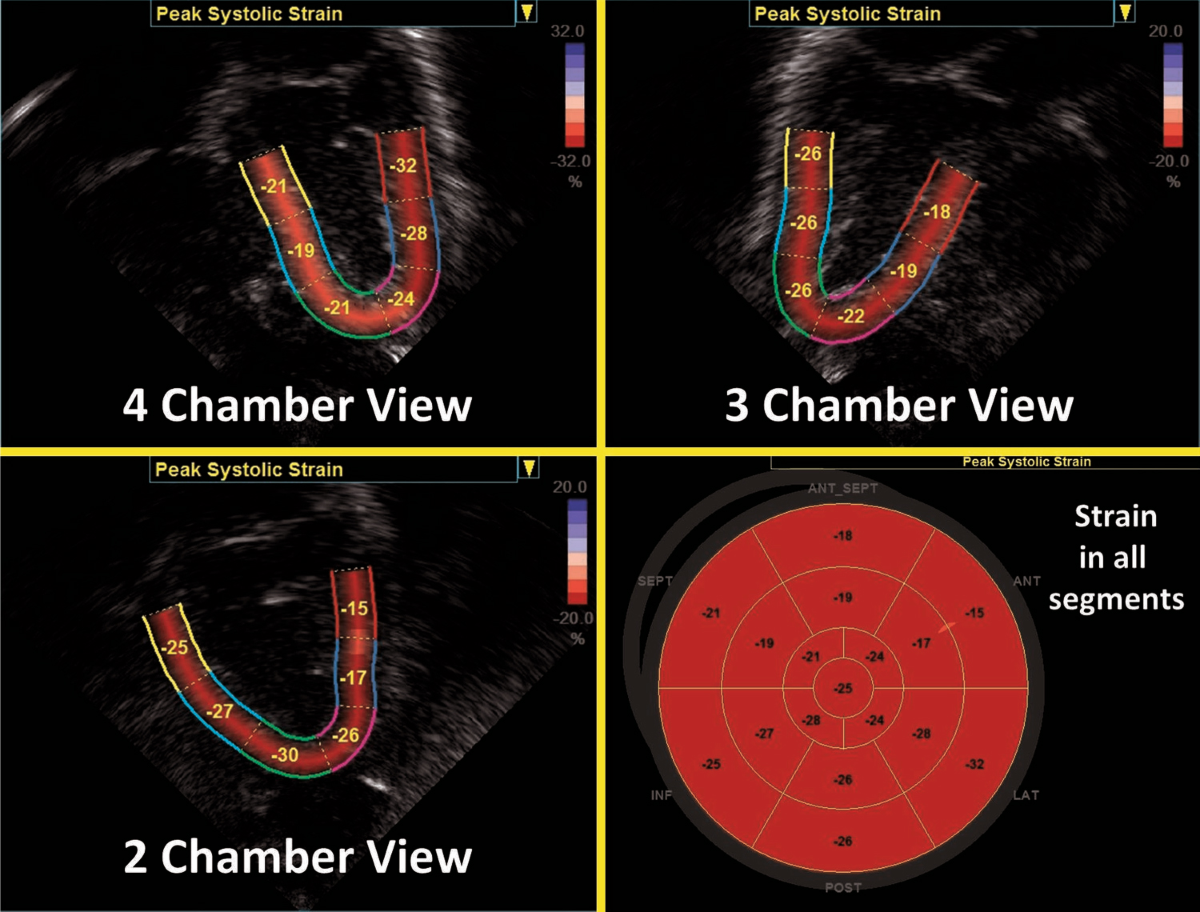

» Interpreting strain echo (98) 사진

Interpreting strain echo (98) 사진